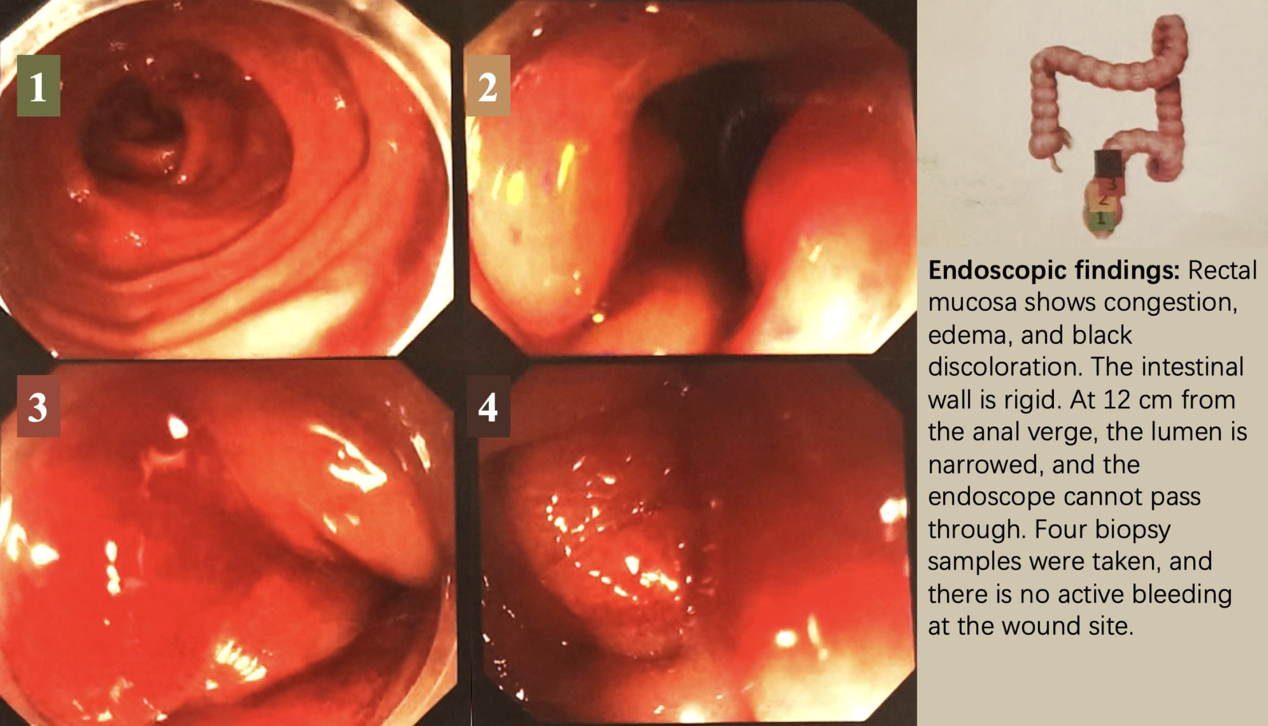

CT检查显示直肠壁增厚(图1),结肠镜检查发现距肛缘12 cm处黏膜改变伴狭窄(图2)。

活检证实为转移性乳腺癌,免疫组化示:P53(突变型表达),CK(+),INSM1(-),Ki-67(50%);Rb(+),CD56(-),Syn(-),CgA(-),GATA3(+),CDX2(-),ER(-),PR(-),HER2(1+),GCDFP15(-),SSTR2(-)。上述结果证实直肠病灶为原发性乳腺癌转移。